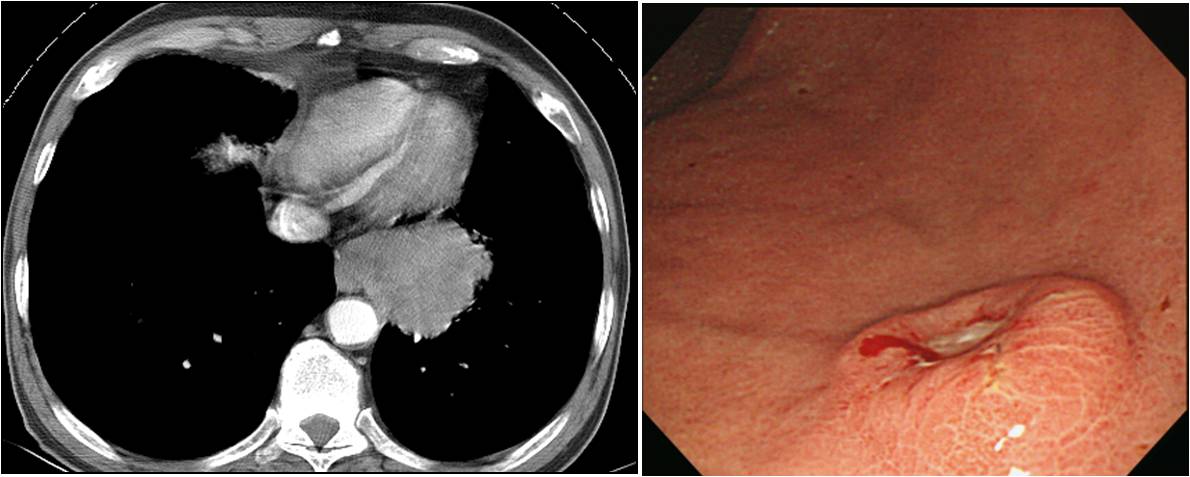

2025-2-9. Æó¾Ï À§ÀüÀÌ

Æó¾Ï (large cell neuroendocrine carcinoma) À§ÀüÀÌ